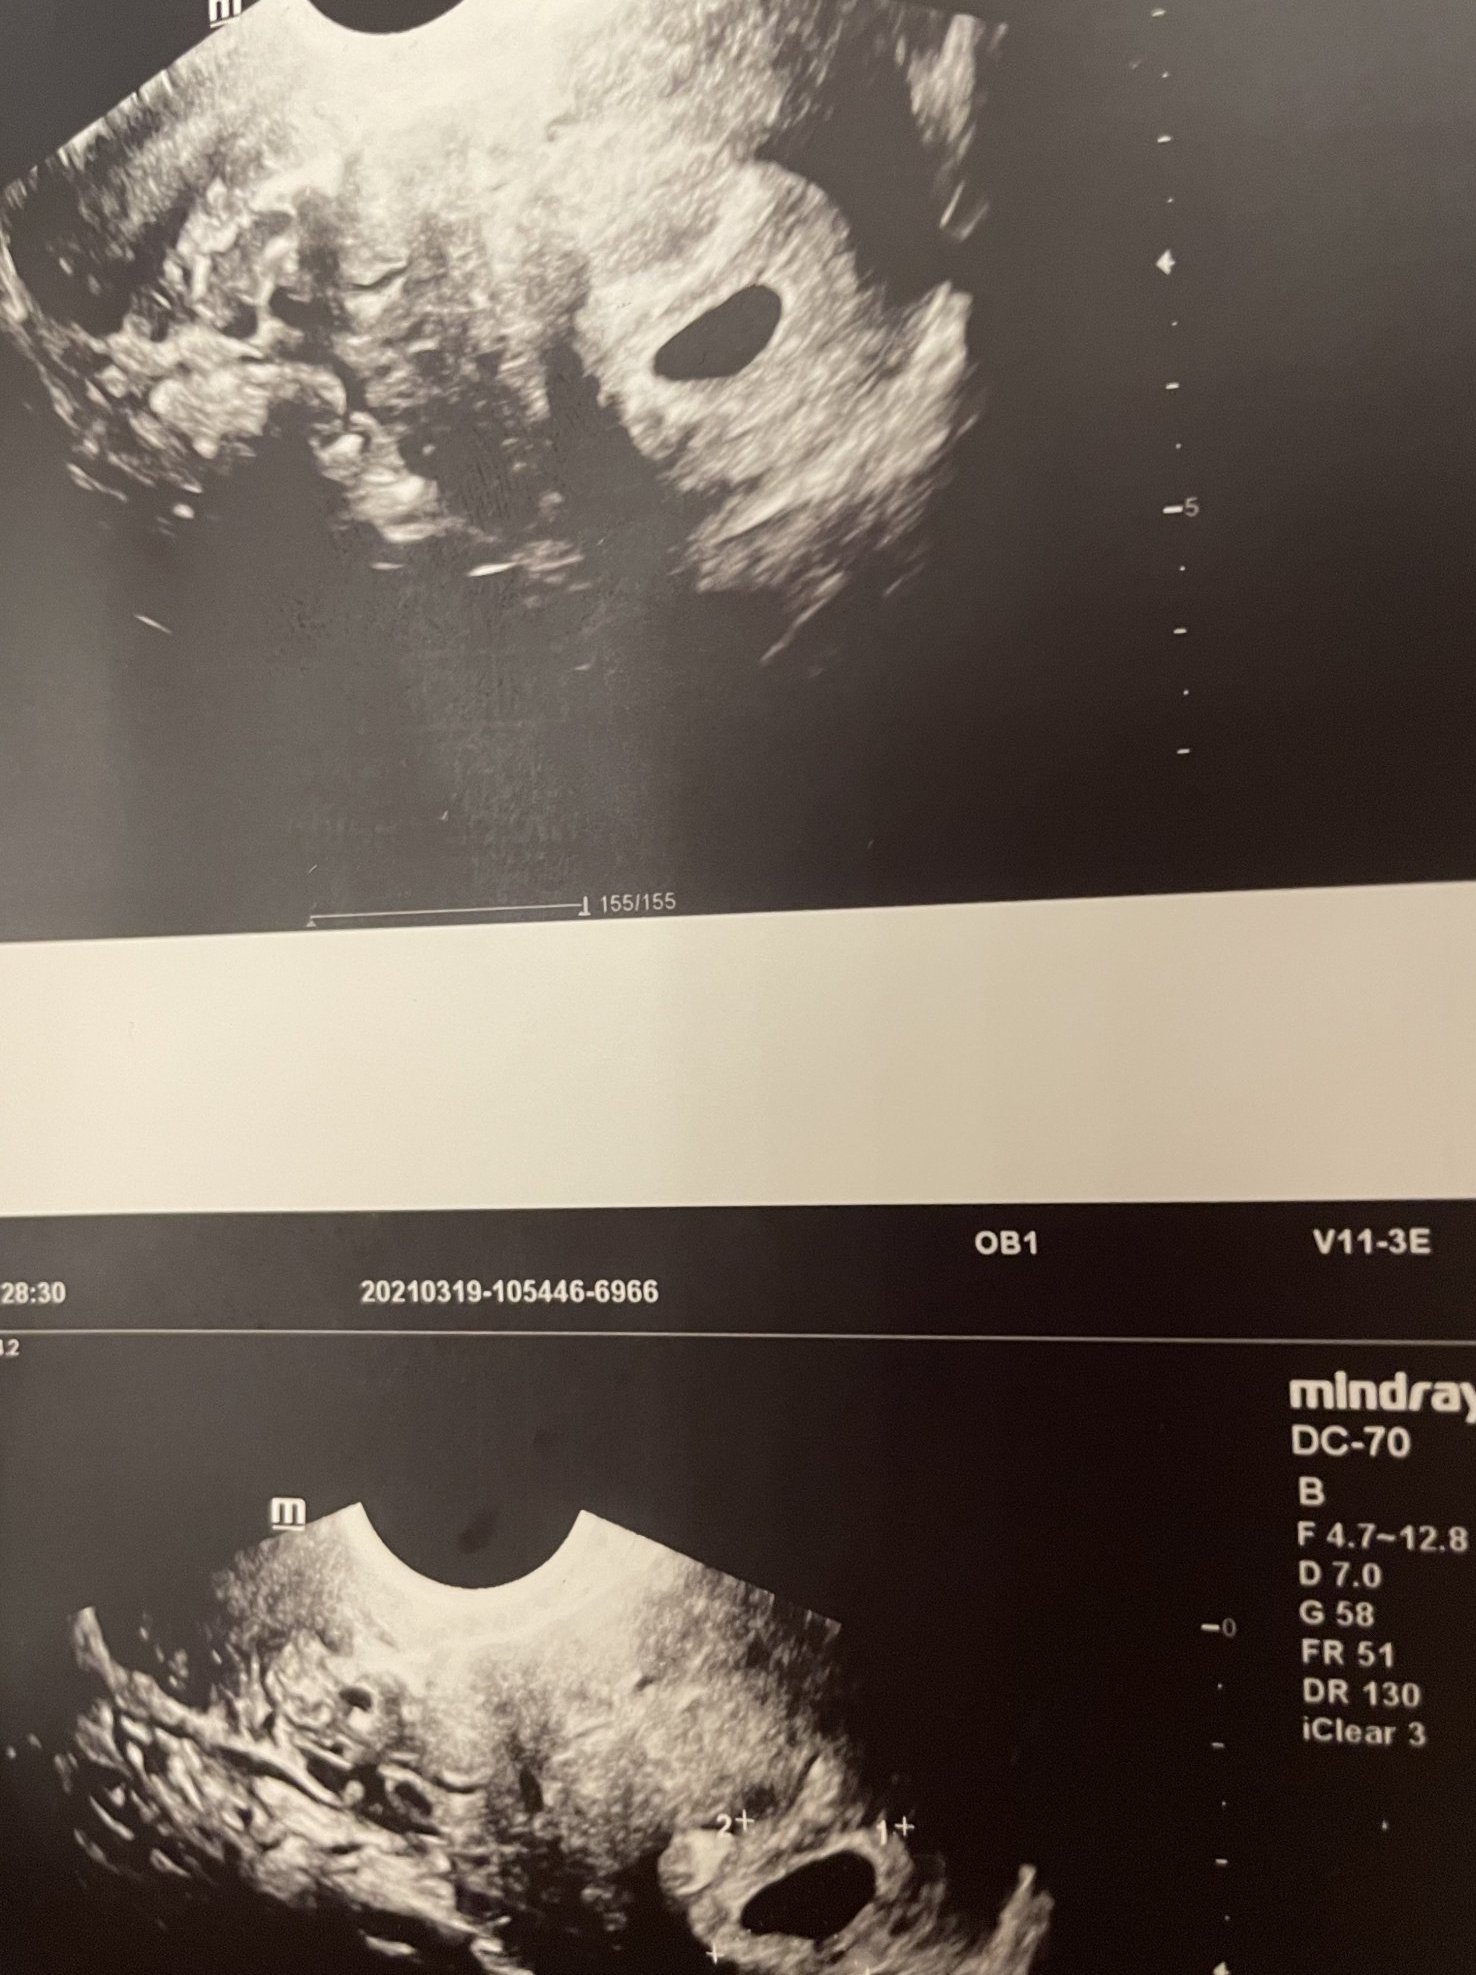

Казаха ми само че съм забременяла по-късно, т.е. била съм с по-късна овулация, но каза, че не вижда нито ембрион нито мехурчето и това много ме притесни...иначе плодния сак миналата седмица беше 6мм, а сега е цели 22мм

Забравих да прикача снимки. Това е от миналата седмица , а това от вчера